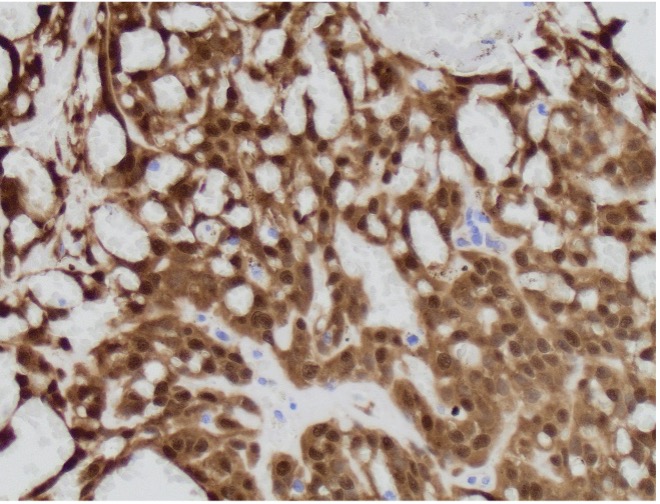

A 64 year-old man with history of clear cell renal cell carcinoma s/p nephrectomy (2021) presents with scrotal pain and firmness. Ultrasound reveals a 2 cm solid lesion. Serum tumor markers (hCG and AFP) were normal. The tumor was negative for SALL4, OCT3/4, AFP, and showed focal patchy positivity for pancytokeratin (focal). PAX8 was weakly positive. Additional stains are displayed in the pictures.